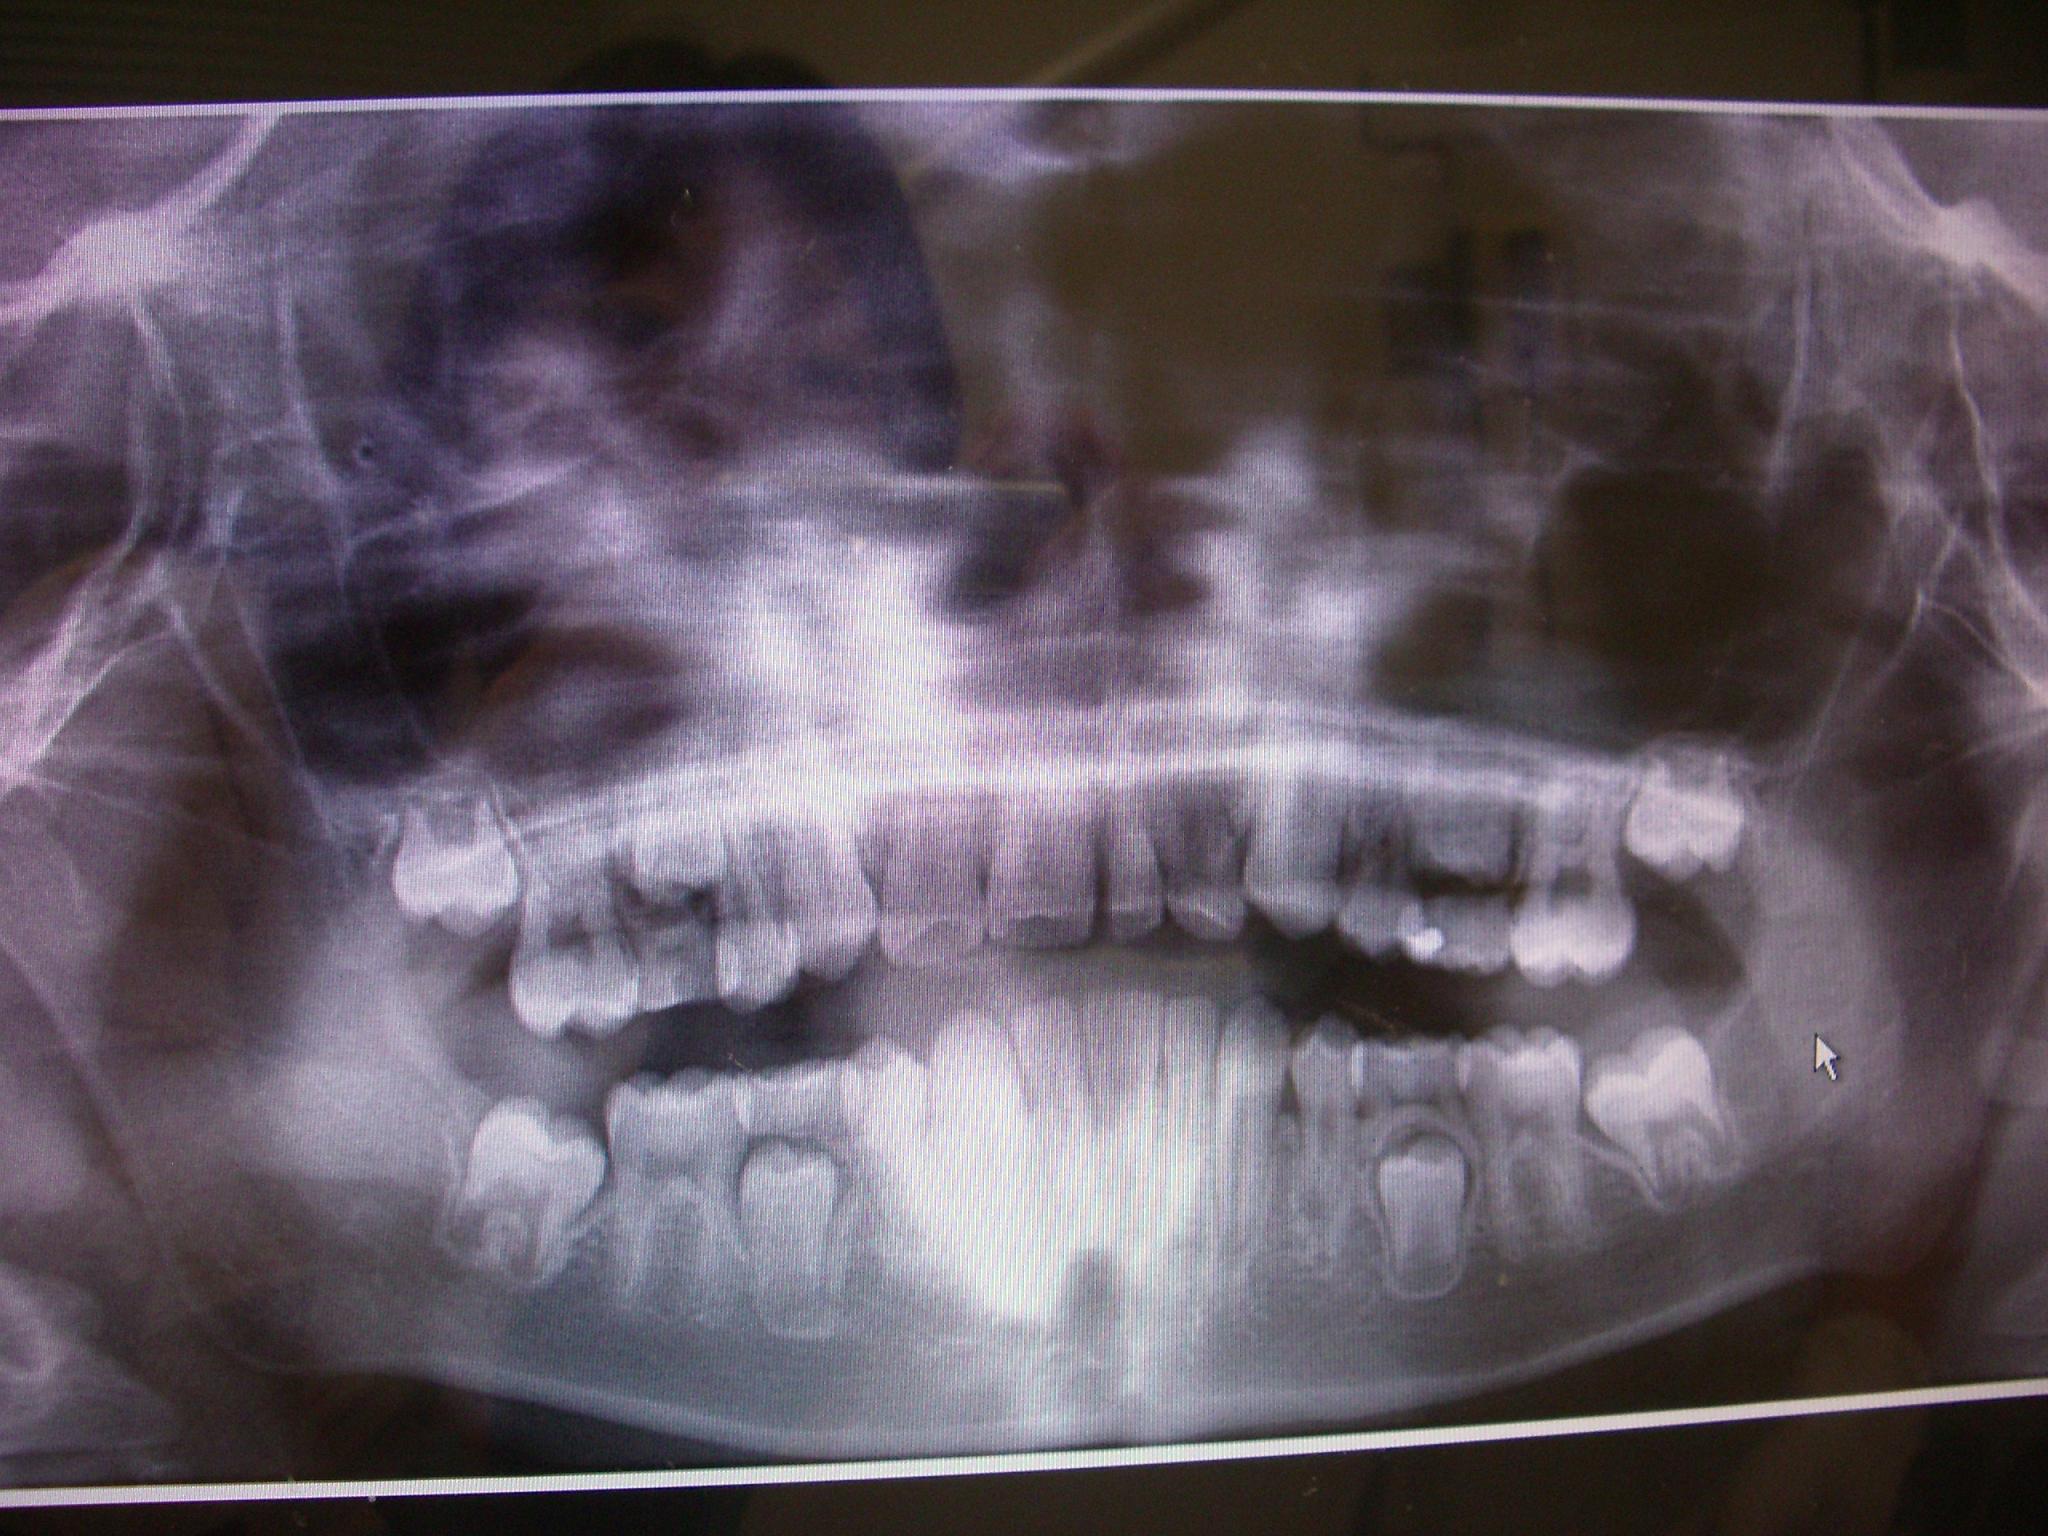

写真を添付させていただきます。どなたかご回答いただきたくお願い致します。

画像1IMGP5140 -  画像2IMGP5143 -

個人的には、お子さんの年齢とレントゲン上での所見と、添付されましたお写真、そして今までの治療経緯から総合的に判断致しまして、抜歯されたほうが良いのではないかと思います。

現在腫れがある乳歯の下には、萌出の待機待ちをしている継続永久歯があります。(右上永久歯の5番、右上第二小臼歯)

添付して頂いたのはパノラマ・レントゲンですので、細部までははっきりとは見えませんが、乳歯の歯根が既に広範囲に渡って吸収されていますし、永久歯の歯胚の上に骨の透過像(破壊)も認められています。

その上、今までの治療経緯を振り返りますと、根管の中の汚染、感染はかなり深刻になっているはずですから、通常の乳歯の根管治療を施しても予後は芳しくないと思われます。

このまま、感染された環境の中に萌出待機中の永久歯が浸かったままでいるほうが、個人的には心配です。

生え変わりの年齢なども考えますと抜歯されたほうが良いのではないかと思いますよ。

パノラマ画像での所見になりますが、(画像があまり良くないので、はっきりと見えない部分もありまして・・・)

右上2番(側切歯)と右下2番が欠損していらっしゃるように見えますし、左上3番の乳歯(そのお隣の歯が永久歯2番なのか乳歯2番なのか定かではありませんが・・・・・)と右上3番の永久歯の高さが同じ位置にあり、上下の中央門歯の中央線がずれております。

実際にお口の中を診ておりませんので、正しいのかどうか分かりませんが、どうでしょうか。